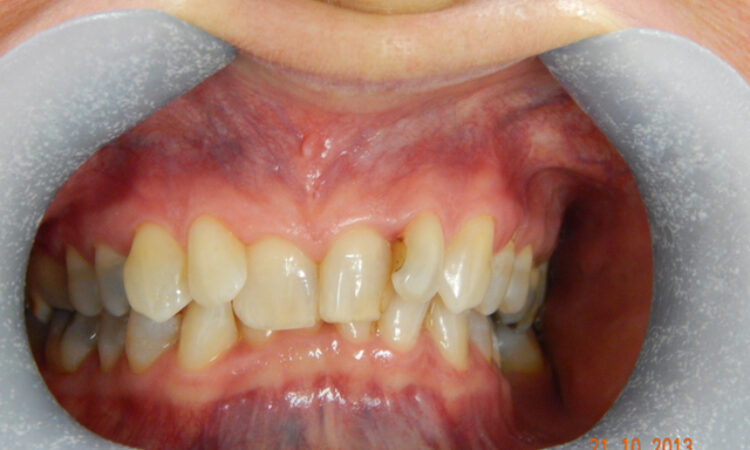

Before - puredental After - puredental

Case 19 - Invisalign®